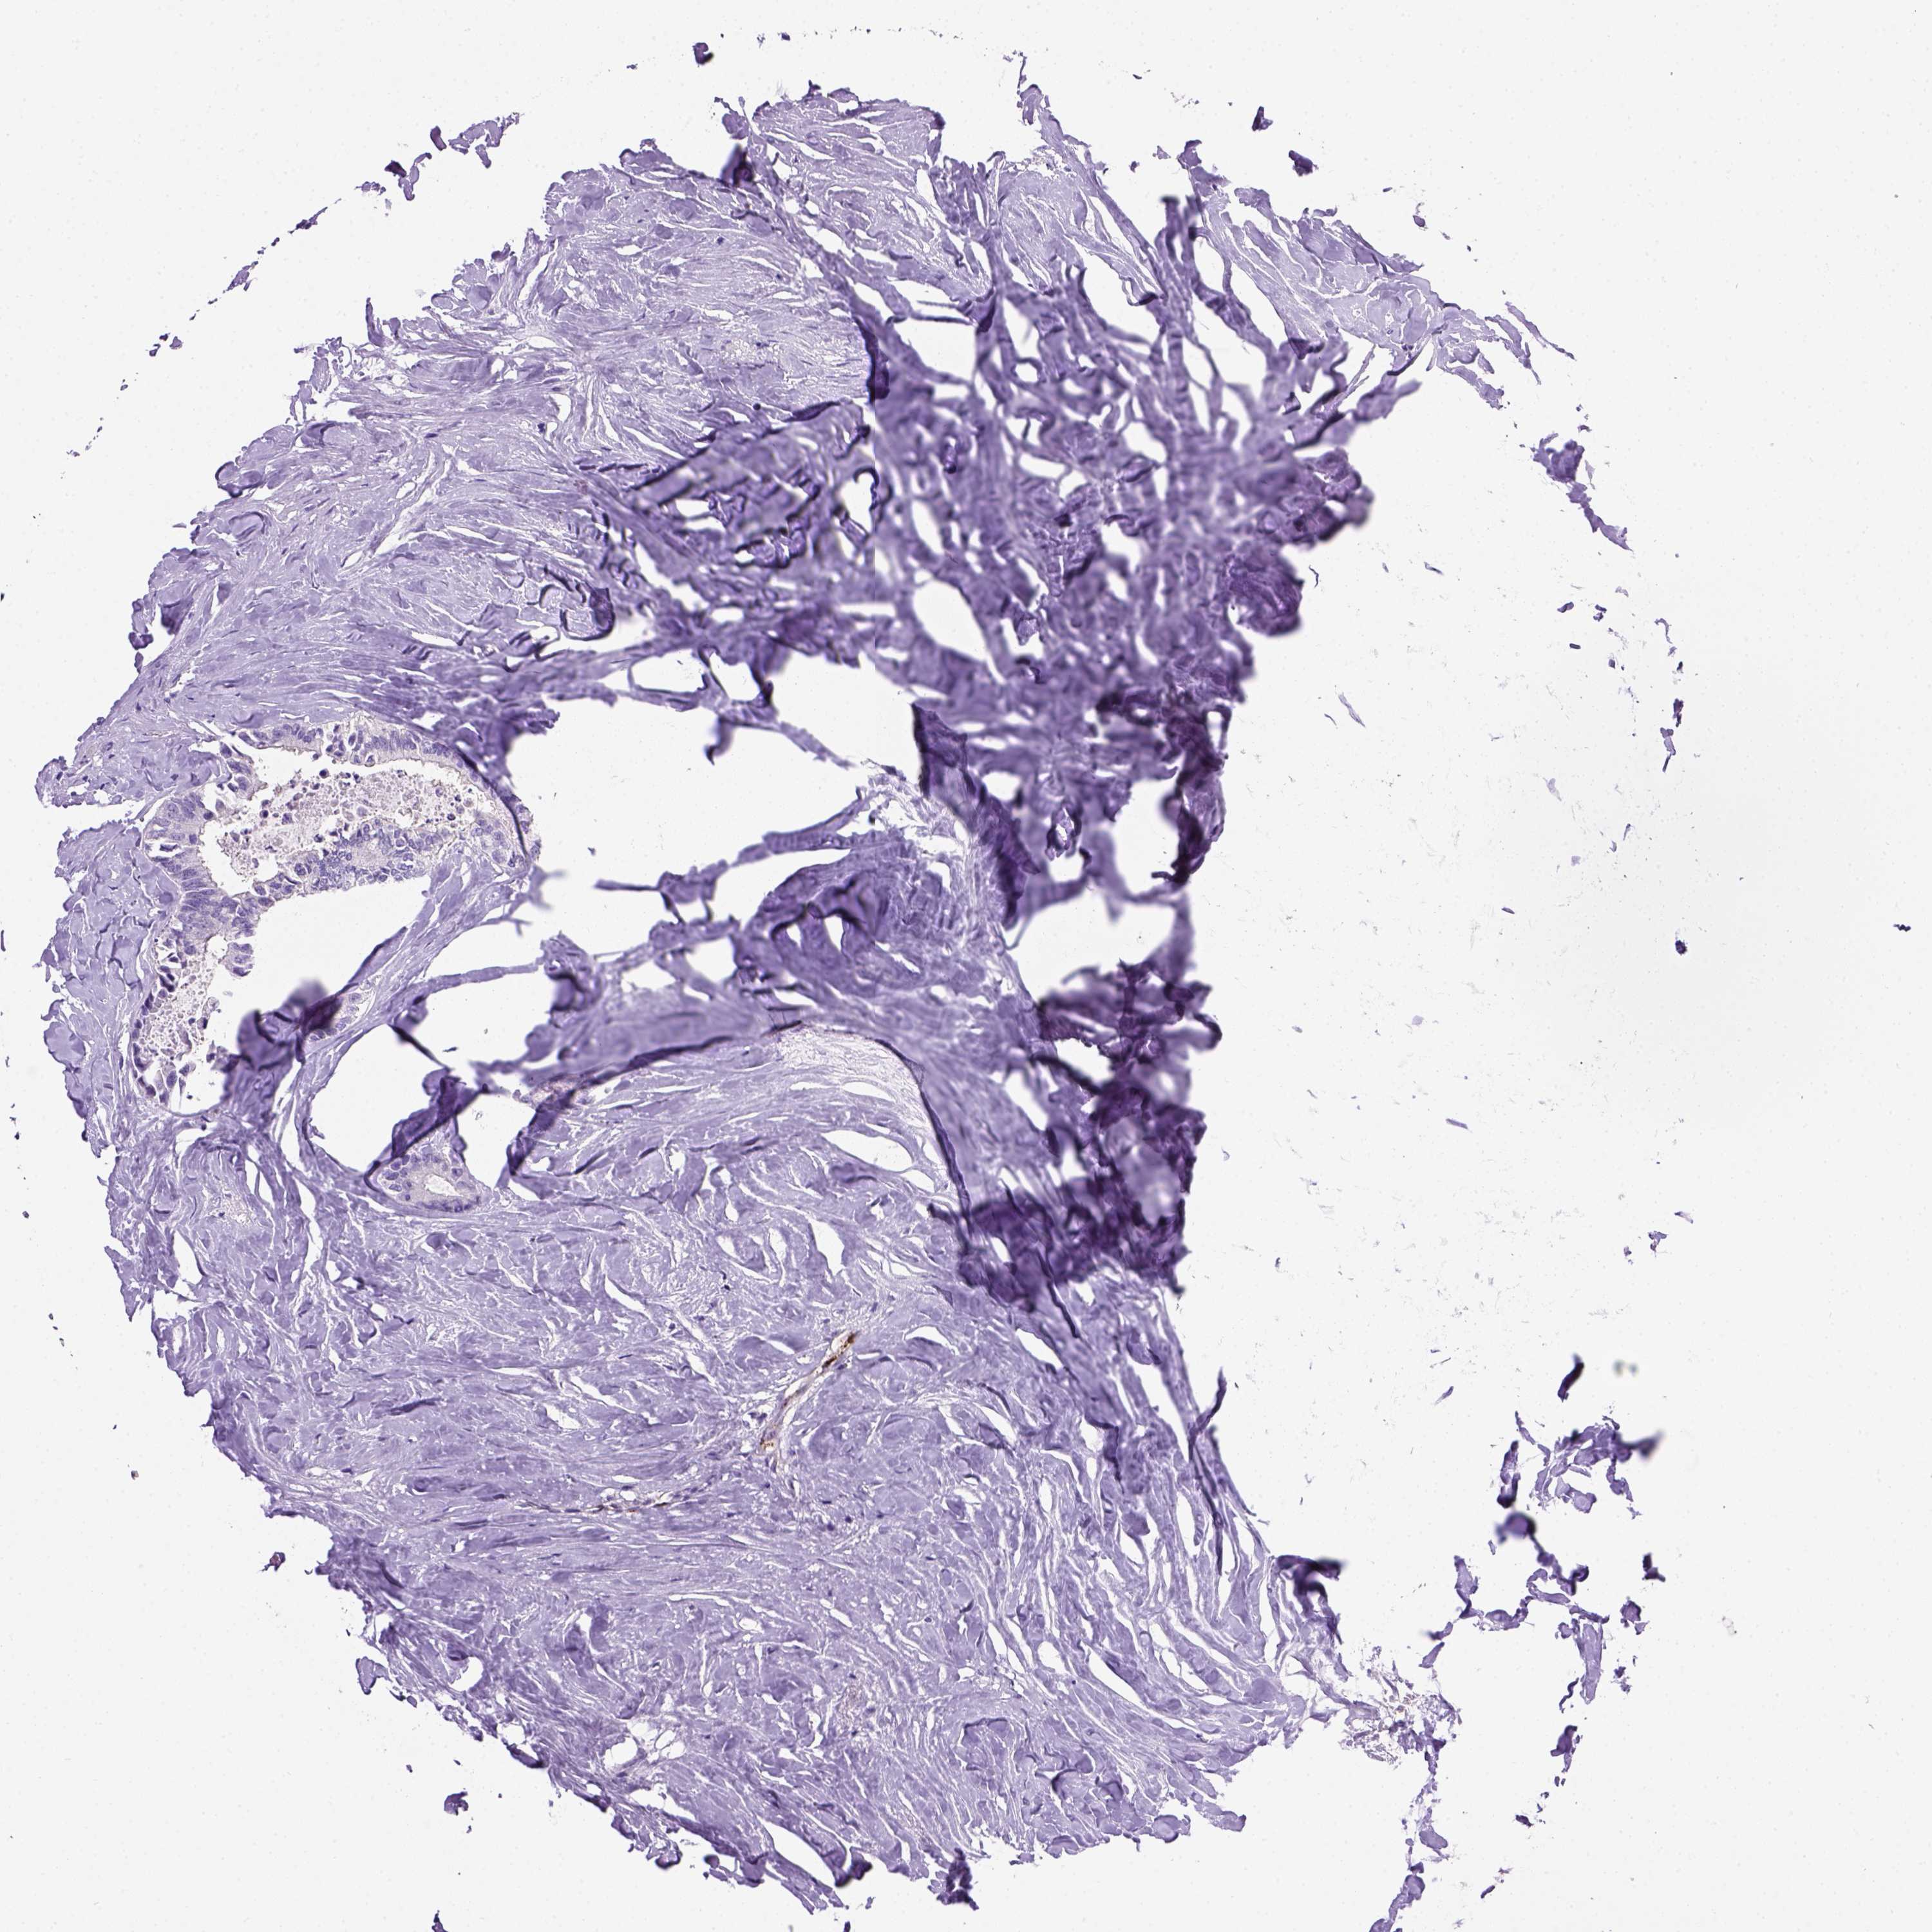

CANCER COLORECTAL CANCER Show tissue menu

COAD TCGA COAD VALIDATION READ TCGA READ VALIDATION PROTEIN COAD CPTAC PROTEIN EXPRESSION

ANTIBODIES

AND

VALIDATION